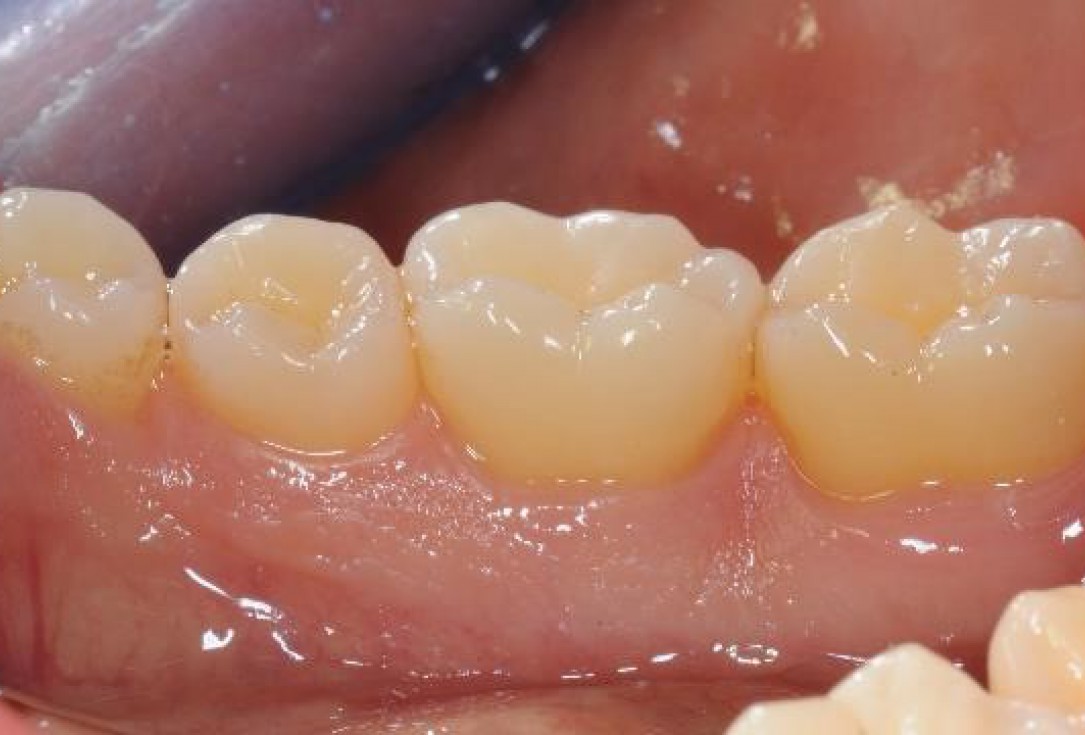

19/22 - Long term follow up: clinical situation 6 years post-operative. Buccal view.

Deep intrabony defects treated using Straumann® Emdogain® - Dr. M. Stefanini